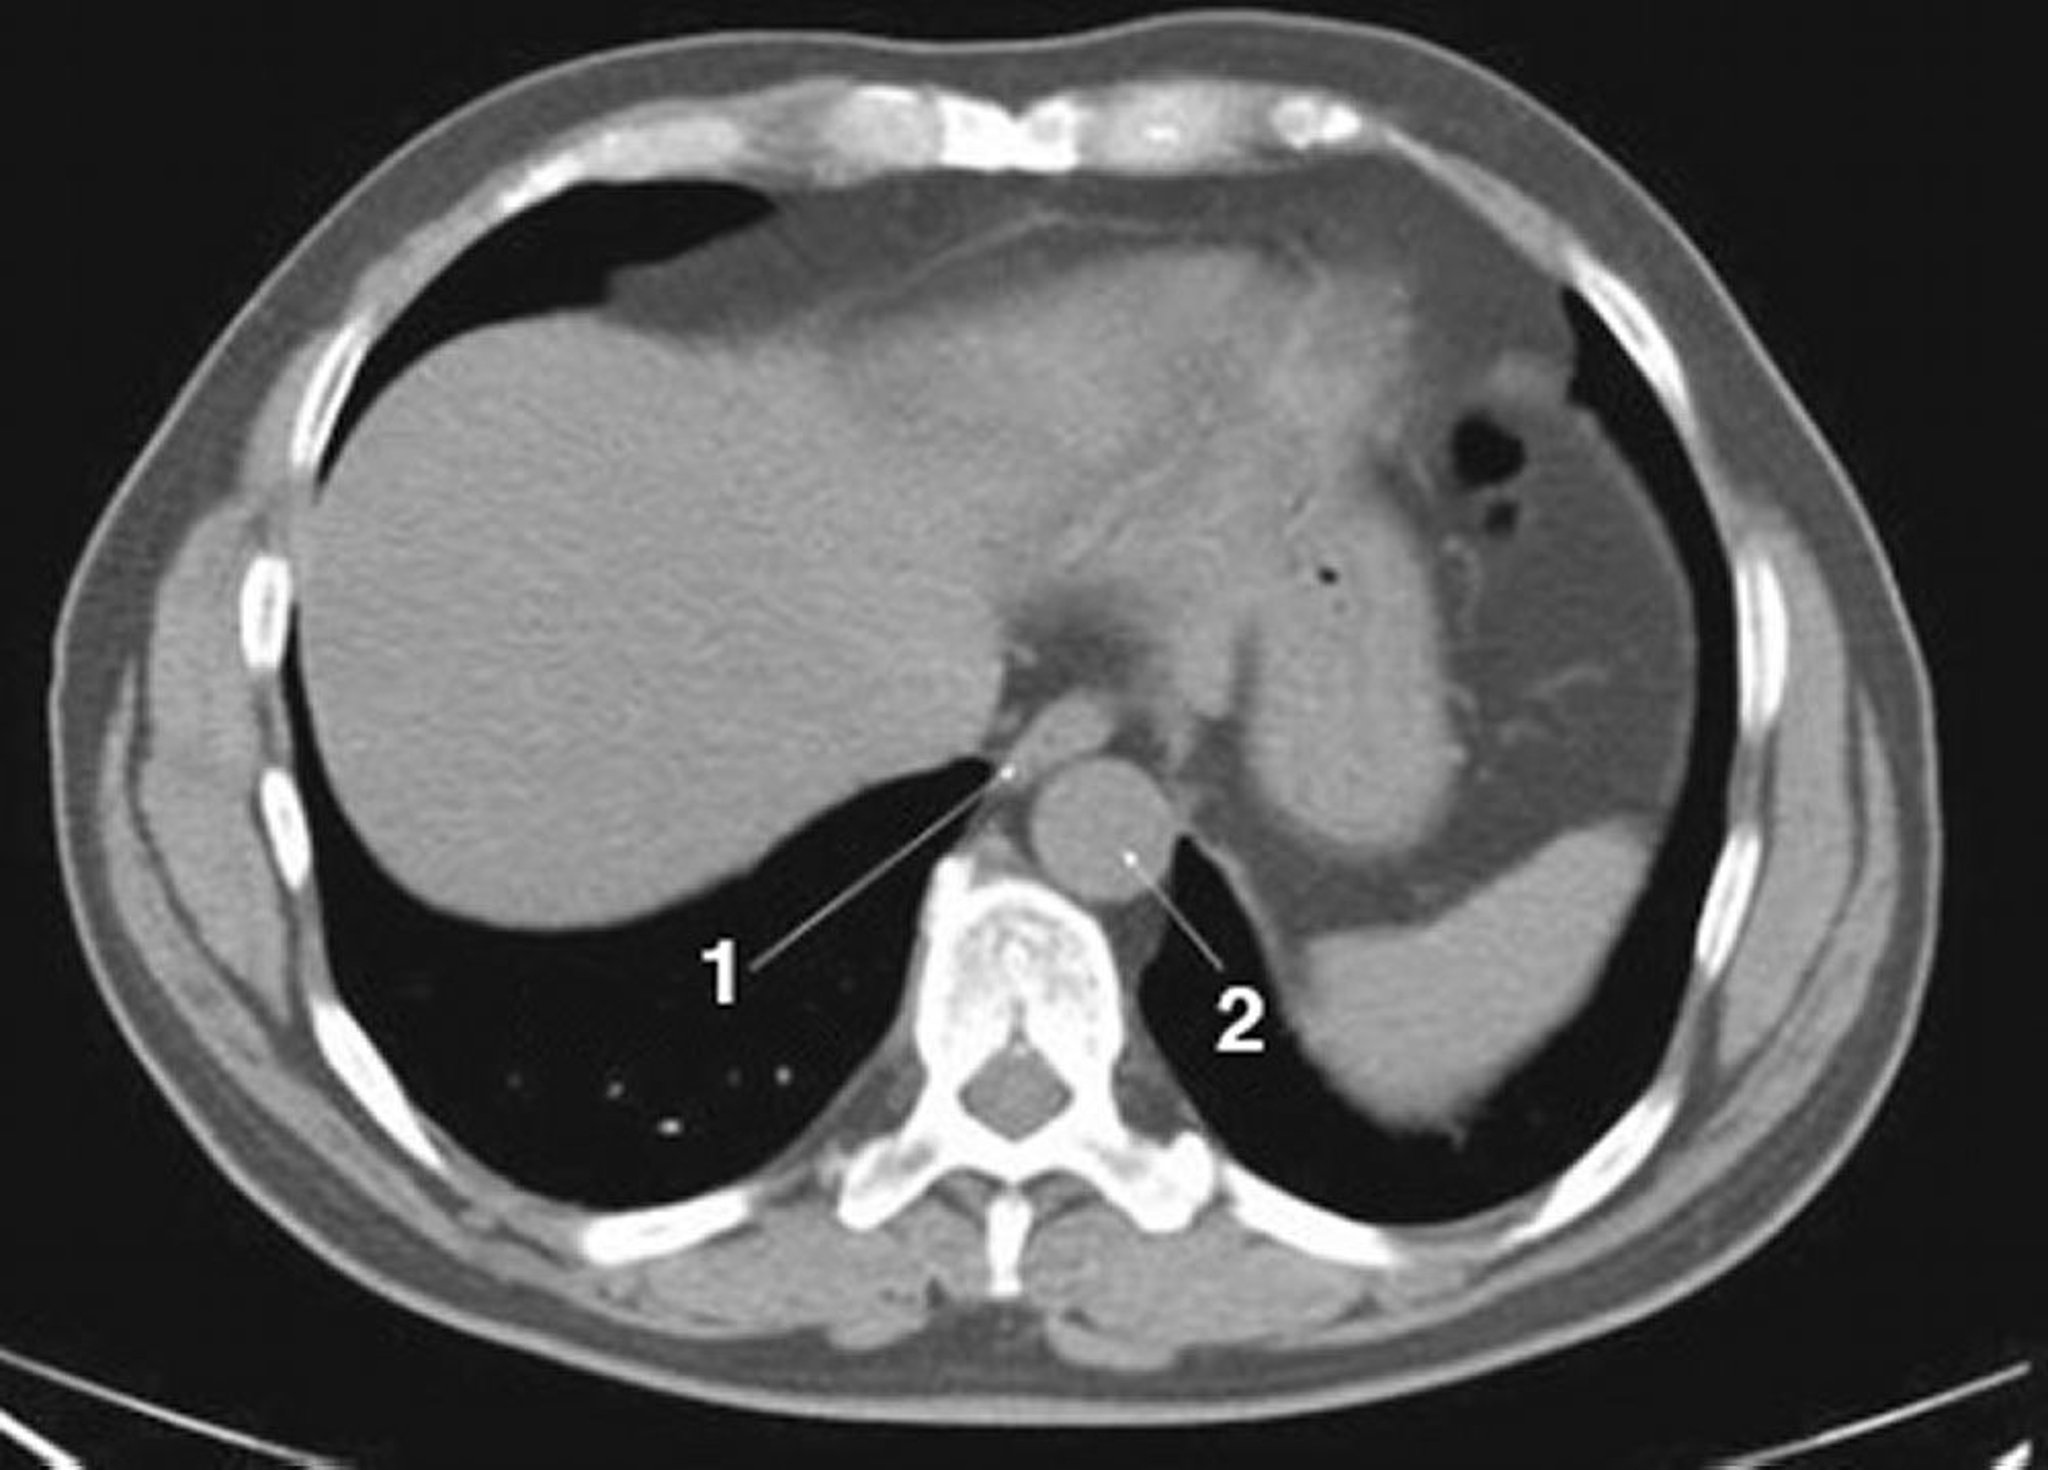

正常解剖を示した腹部および骨盤の単純CT画像(スライド1)

1 = 食道;2 = 大動脈。